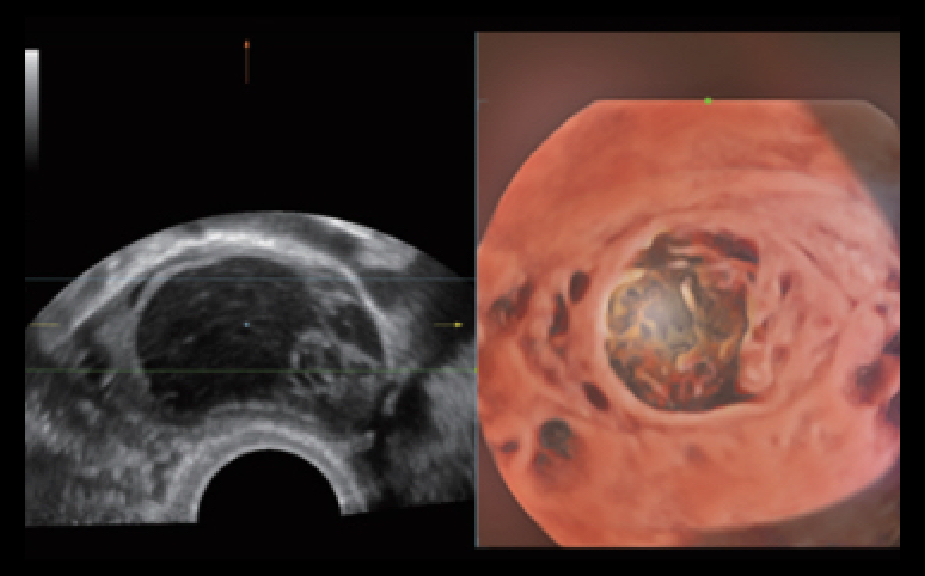

Nuewa I9? ??? ???? ?? ??? ?? ??? ???? ?? ??? ???? ???? ??? ?????. ??? ??? ??? ?? ????? ?? ???? ???? ???? ???? ??? ???? ??? ??? ???? ??? ???? ??? ?? ?????.